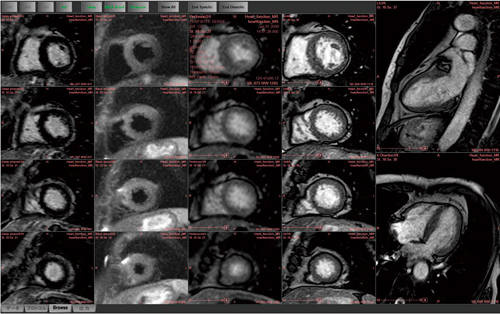

解析結果については,高解像度ワイドモニタに最適化されたレイアウトを備えることで,心機能に関する値だけでなく,壁厚,壁運動,壁厚変化率など複数のBull's eye mapを1画面上に表示することが可能となった(図2)。例えば,動画で短軸画像の壁運動と,Bull's eye mapで壁運動や壁厚変化率などの局所機能を同時に観察することが可能である。解析結果を比較分析することは,読影効率の向上に繋がるものと期待できる。

図2 MR心機能解析結果に最適化された表示レイアウト 複数のBull's eye mapを1画面上に表示可能

図2 MR心機能解析結果に最適化された表示レイアウト

複数のBull's eye mapを1画面上に表示可能